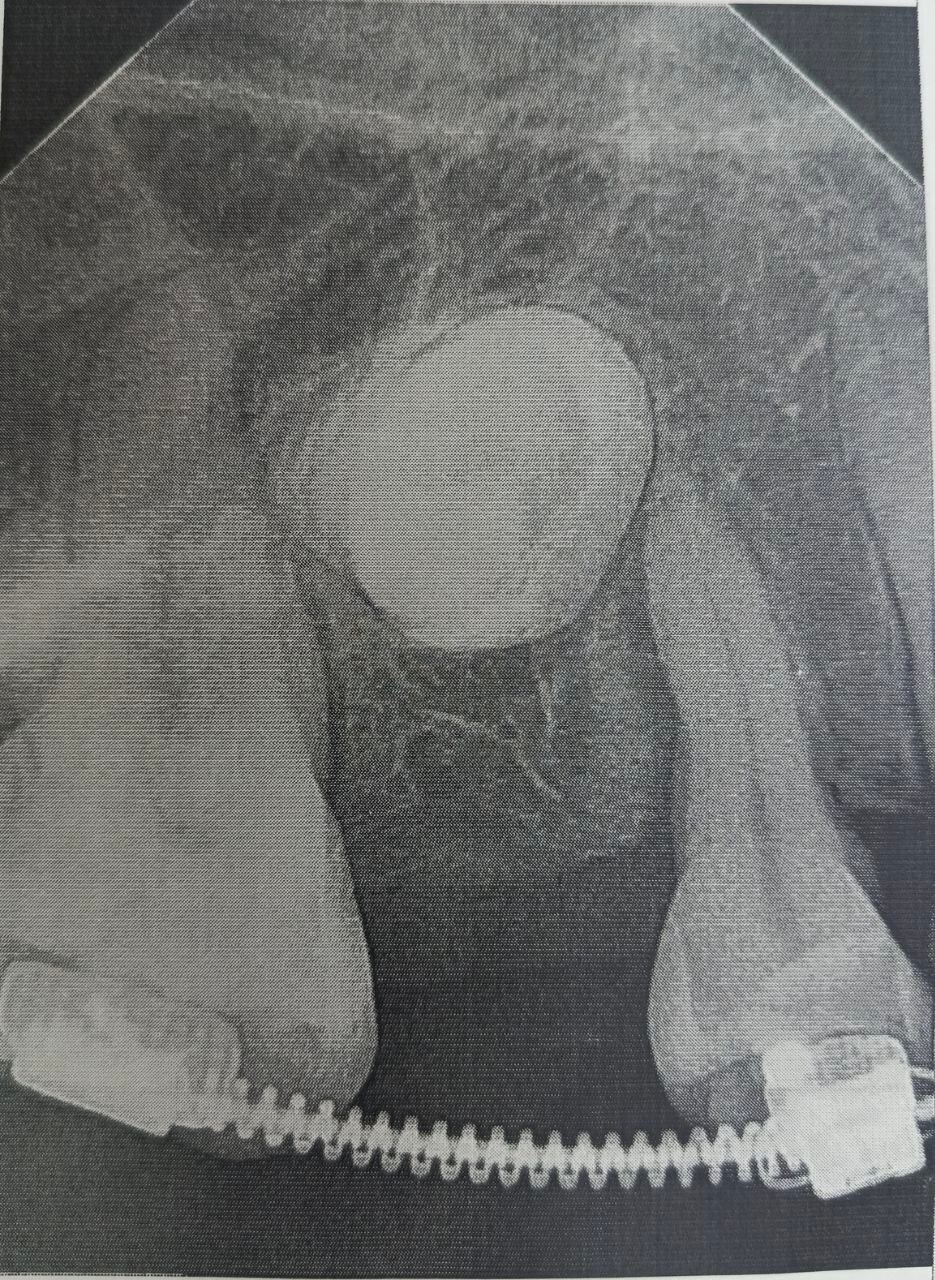

Сначала пациентке установили брекет-систему, полтора года с ее помощью в зубном ряду создавалось место. Когда пространство было подготовлено, хирурги провели операцию: раскрыли десну, чтобы обнажить коронки непрорезавшихся зубов, и зафиксировали на них специальные ортодонтические кнопки.

С помощью миниатюрных пружин и рычагов, подключенных к брекет-системе, зубы начали медленное движение.